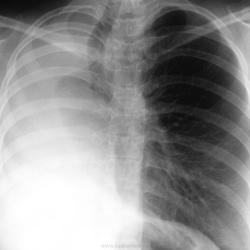

Патологические состояния после перенесенного туберкулёза. Энн Н. Leung. На фоне снижения прозрачности кальцификаты. Состояние после правосторонней пульмонэктомии. Ср, 20/07/2011 - 02:22 #1 Катенёв Валенти... Не на сайте Был на сайте: 7 лет 6 месяцев назад Зарегистрирован: 22.03.2008 - 22:15 Публикации: 54876 Экстраплевральная "пломба"Приложения: Пнд, 08/08/2011 - 22:18 #2 Катенёв Валенти... Не на сайте Был на сайте: 7 лет 6 месяцев назад Зарегистрирован: 22.03.2008 - 22:15 Публикации: 54876 Экстраплевральная "пломба"Приложения: Вс, 12/02/2012 - 21:09 #3 Aleksandra85 Не на сайте Был на сайте: 14 лет 3 месяцев назад Зарегистрирован: 09.02.2012 - 20:26 Публикации: 28 ОГО! впервые такое вижу!! Чт, 15/03/2012 - 21:53 #4 Катенёв Валенти... Не на сайте Был на сайте: 7 лет 6 месяцев назад Зарегистрирован: 22.03.2008 - 22:15 Публикации: 54876 Торакопластика.Приложения: Втр, 17/07/2012 - 16:38 #5 Катенёв Валенти... Не на сайте Был на сайте: 7 лет 6 месяцев назад Зарегистрирован: 22.03.2008 - 22:15 Публикации: 54876 Посттуберкулёзные измененияПриложения: Сб, 11/08/2012 - 00:57 #6 Катенёв Валенти... Не на сайте Был на сайте: 7 лет 6 месяцев назад Зарегистрирован: 22.03.2008 - 22:15 Публикации: 54876 Продолжение.Приложения: Чт, 27/09/2012 - 16:34 #7 Катенёв Валенти... Не на сайте Был на сайте: 7 лет 6 месяцев назад Зарегистрирован: 22.03.2008 - 22:15 Публикации: 54876 Экстраплевральная пломбаПриложения: Ср, 18/09/2013 - 23:14 #8 Катенёв Валенти... Не на сайте Был на сайте: 7 лет 6 месяцев назад Зарегистрирован: 22.03.2008 - 22:15 Публикации: 54876 Последствия и осложнения туберкулёза http://radiographics.rsna.org/content/21/4/839.full Ср, 05/02/2014 - 11:58 #9 Катенёв Валенти... Не на сайте Был на сайте: 7 лет 6 месяцев назад Зарегистрирован: 22.03.2008 - 22:15 Публикации: 54876 Торакопластика. Приложения: Сб, 10/03/2018 - 09:59 #10 Катенёв Валенти... Не на сайте Был на сайте: 7 лет 6 месяцев назад Зарегистрирован: 22.03.2008 - 22:15 Публикации: 54876 Состояние после наложения олеоторакса. http://www.nejm.org/doi/full/10.1056/NEJMicm1609176 Приложения: Вс, 16/09/2018 - 20:04 #11 Катенёв Валенти... Не на сайте Был на сайте: 7 лет 6 месяцев назад Зарегистрирован: 22.03.2008 - 22:15 Публикации: 54876 торакопластика

Посттуберкулёзные изменения